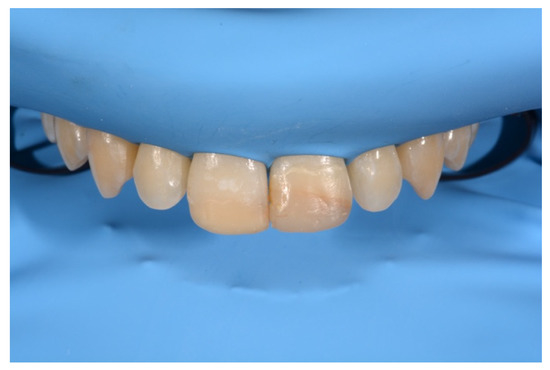

2. Case Presentation

- Molding palatal wall and incisal margin;

- Building interproximal walls with matrices;

- Layering free-hand buccal surface.